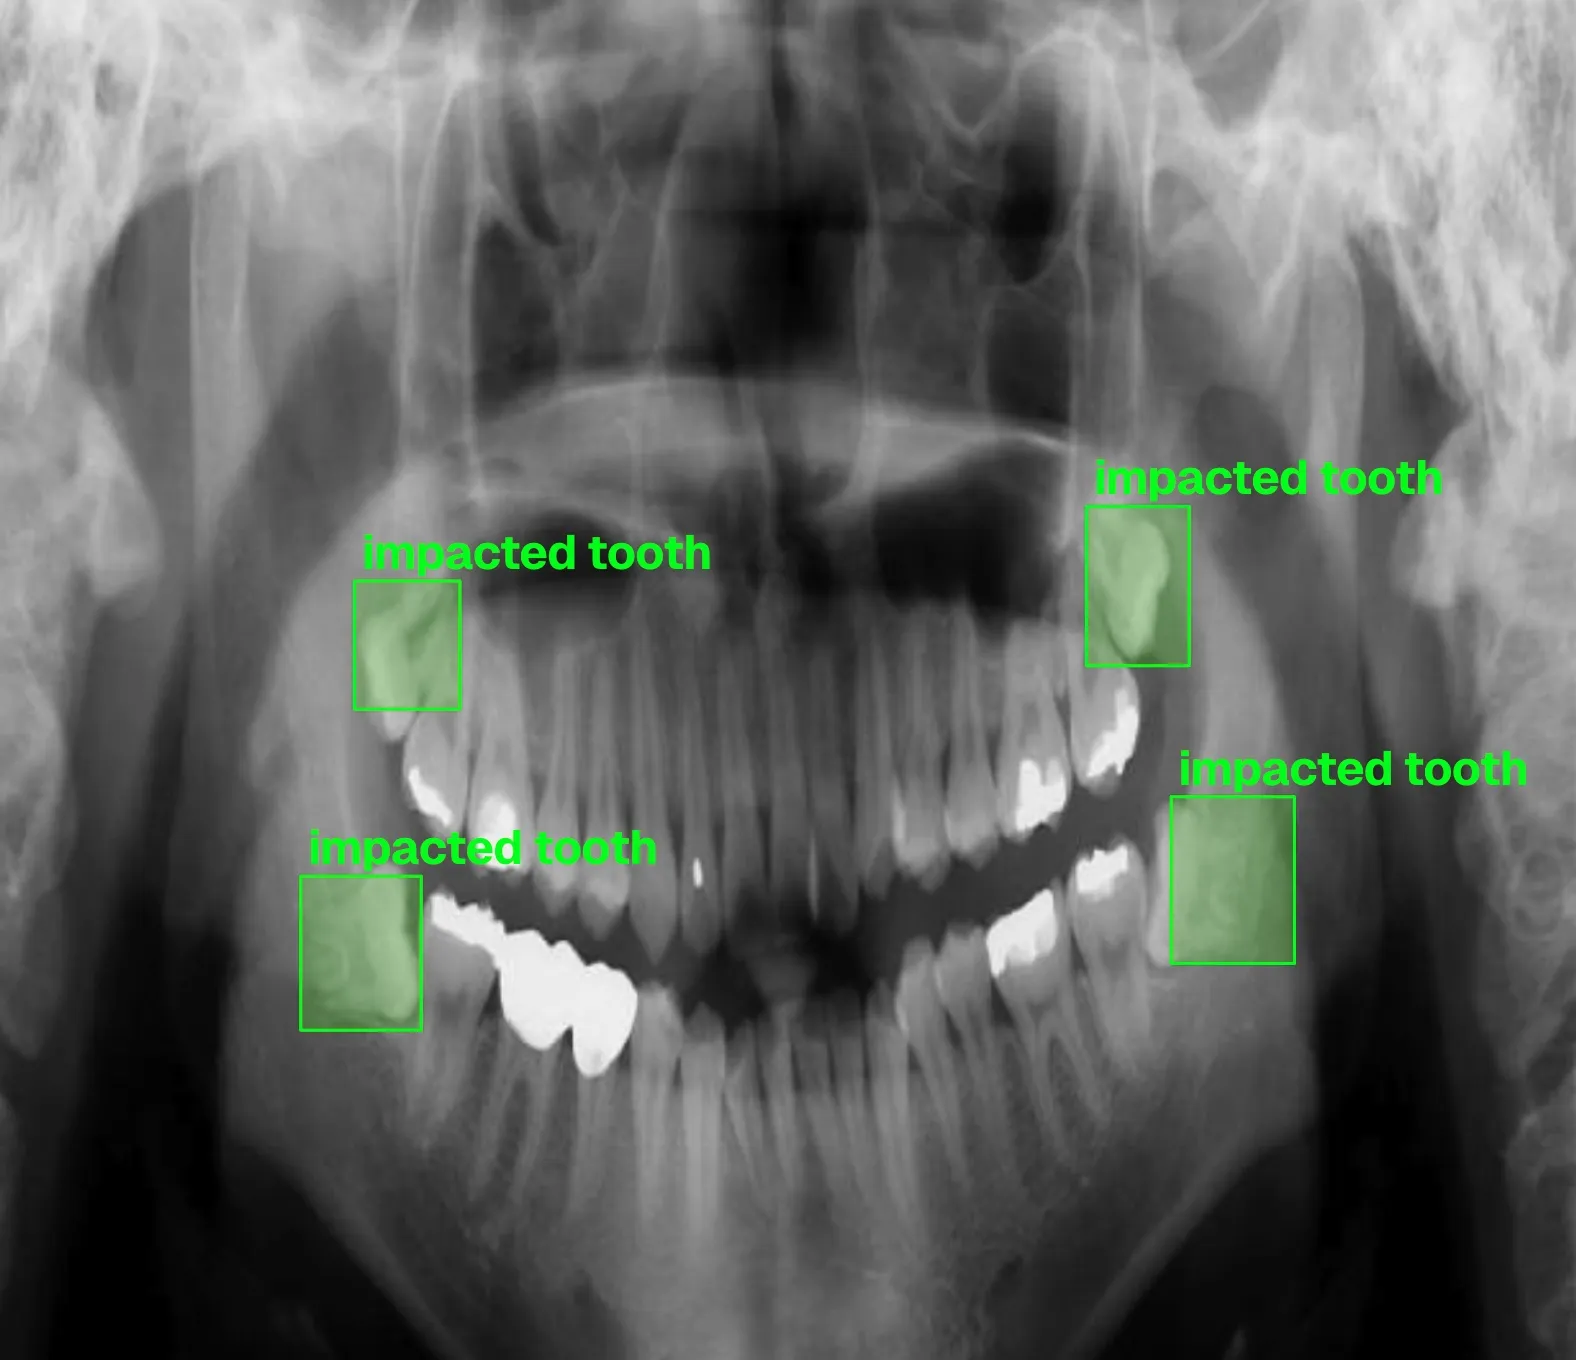

Building computer vision datasets and training YOLO models for automated dental pathology detection on panoramic X-rays.

- Advanced oral surgery including impaction management

Annotating dental X-rays with clinician-grade precision for object detection and OBB tasks.

- •Managed impacted tooth cases now reflected in the 1,000+ image detection dataset

- •Emergency case exposure informed edge-case coverage in training data